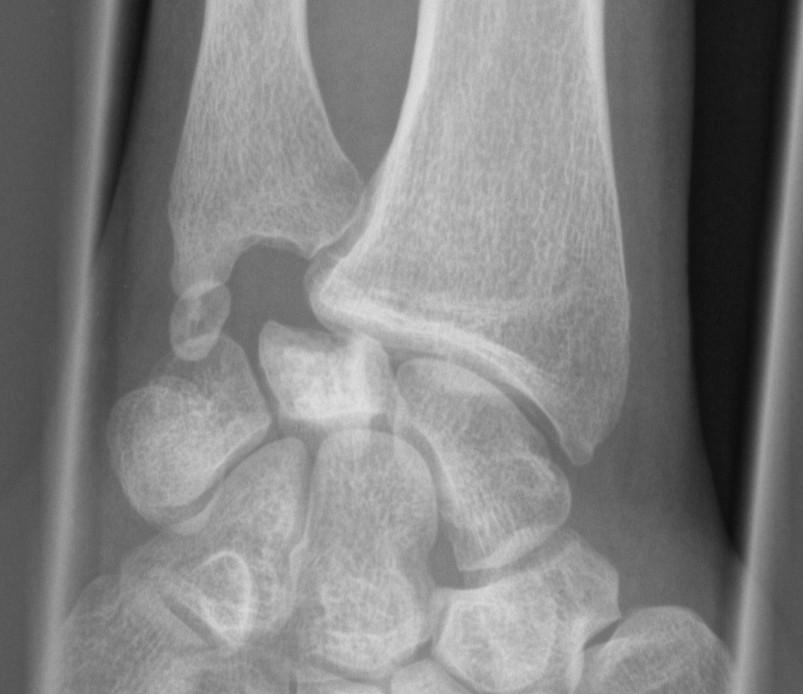

Lunatummalaci er en sygdom, hvor der er forstyrrelse i blodkredsløbet i den måneformede knogle i håndroden (os lunatum).  Røntgenbillede viser typiske forandringer i os lunatum med scleroseret knogle og delvis sammenfald. Desuden ses en udtalt ulna minus variant (ulna er kortere end radius).